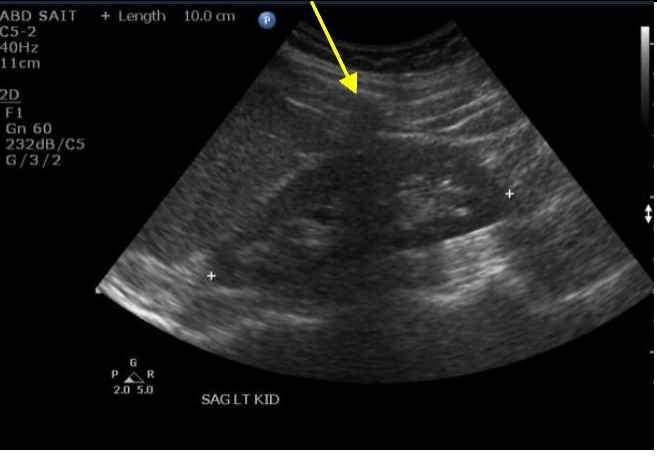

12

Q

What structure (at yellow arrow) is causing the shadow over LK?

A

RIbs